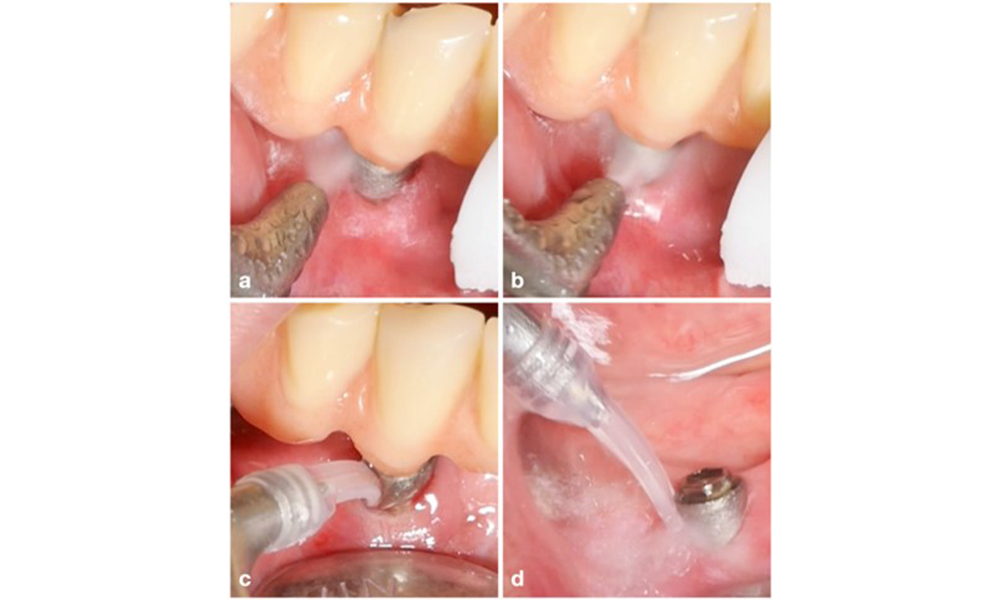

Le concept de traitement de la mucosite péri-implantaire est comparable au traitement de la gingivite. L'approche principale est le contrôle professionnel de la plaque, visant à perturber mécaniquement le biofilm sans altérer la surface de l'implant ou du pilier. Diverses méthodes utilisant des moyens mécaniques sont décrites dans la littérature : curettes, détartreurs (ultra)soniques, dispositifs d'aéropolissage, application de laser, etc. avec ou sans utilisation d'agents antimicrobiens. Actuellement, aucune méthode ne s'est avérée systématiquement supérieure aux autres, tandis que l'utilisation d'antibiotiques systémiques n'est pas recommandée pour le traitement de la mucosite péri-implantaire (Dommisch et al. 2022 ; Gennai et al. 2023 ; Hallström et al. 2012 ; Herrera et al. 2023 ; Verket et al. 2023).

Le choix de l'équipement dépend des circonstances cliniques, comme la distinction entre le tartre et la plaque molle. Ainsi, en cas de tartre, il convient d'utiliser d'abord des curettes en titane ou en plastique, ou des embouts spécialement conçus pour les détartreurs à ultrasons, puis un appareil d'aéropolissage (figure 7). Dans les cas où il n'y a qu'une accumulation de plaque molle, un dispositif d'aéropolissage peut suffire. Les dispositifs d'aéropolissage sont faciles à utiliser pour l'opérateur et le patient et sont au moins aussi efficaces que les instruments standard (Schwarz et al. 2015a).